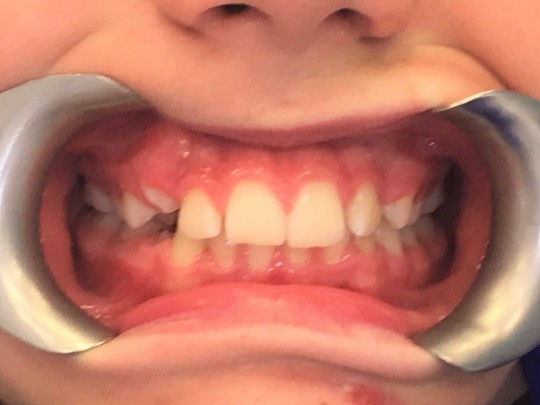

Sometimes some problems can occur. Common problem is a gap between the incisors. This gap is usually closed when the permanent canines erupt. Sometimes a permanent tooth erupts before the milk tooth has fallen out. The tooth usually falls out later, or a dentist extracts it.

+

Fig. 9. Mixed dentition